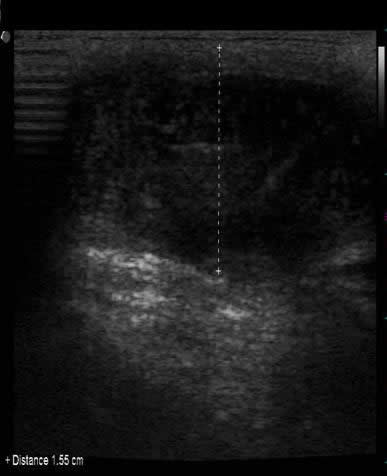

2) Ultrasonografía musculoesquelética de control:

Fotos 2 A y B. Imágenes de corte longitudinal articulación del codo. (A) Se observa bolsa sinovial con menor contenido hipoecogénico, delimitada por bandas hiperecogénicas más delgadas.

(B) Obsérvese mayor detalle